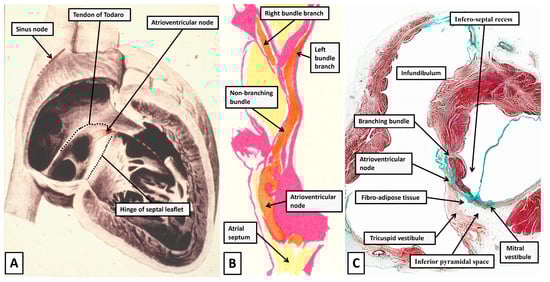

3.1. The Historical Perspective

3.2. The Anatomy of the Inferior Pyramidal Space

3.6. Putting the Atrioventricular Node Back into the Heart